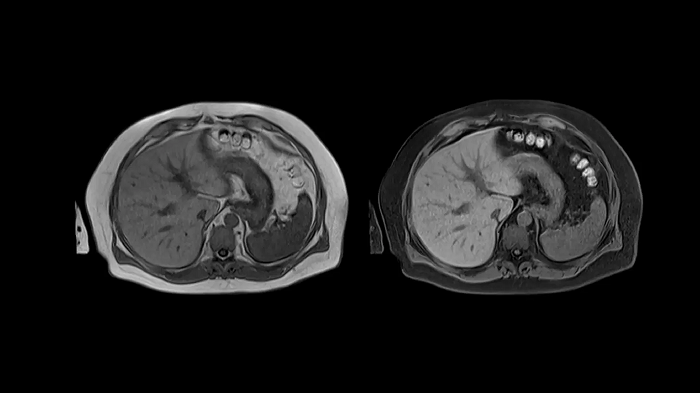

T1 VIBE Dixon with CAIPIRINHA

Benefit from Siemens Healthineers’ dedicated CAIPIRINHA acceleration to gain a complete abdominal volume within a single breath-hold. The Dixon technique offers outstanding fat-water separation for a flawless representation of the abdominal anatomy.

- Contour L Coil

- Spine Coil

Image Courtesy: University Hospital Erlangen, Germany | Image-ID: 4aaaa0458